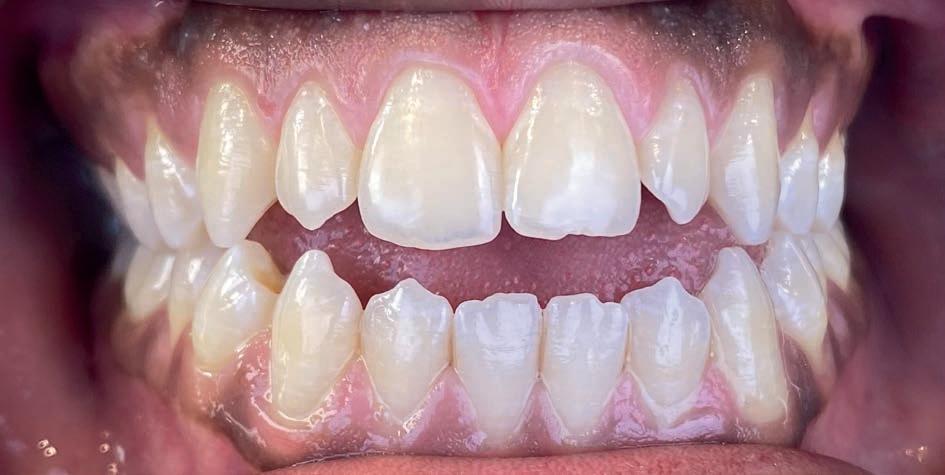

Casus: Jorn

Niet-chirurgische correctie van een Klasse III-relatie

Patiënt: Jorn (18 jaar)

Behandelduur: 15 maanden

Behandeling: Damon Ultima brackets en elastieken

Jorn en zijn vader kwamen via Google bij Clover

Orthodontie terecht, nadat hij elders een chirurgisch behandelvoorstel had gekregen. Als actieve voetballer paste een operatie niet in zijn leven. Hij presenteerde zich met een skeletale Klasse III-relatie, anterieure kruisbeet, negatieve sagittale overbeet en een concaaf profiel.

Behandelstrategie

Er werd gekozen voor een behandeling met Damon Ultima brackets en een strak gepland elastiekprotocol. Vanaf het begin droeg Jorn Klasse III-elastieken om de sagittale discrepantie te corrigeren. Dankzij de precisie en lage frictie van Damon Ultima konden we transversaal én sagittaal corrigeren zonder chirurgische ingreep.

Het eindresultaat bestond uit een stabiele Klasse I-occlusie met een duidelijk verbeterd profiel. Er zijn geen extracties of chirurgische ingrepen uitgevoerd. Voor de retentie werd gekozen voor vaste spalken in combinatie met nachtbeugels, om het bereikte resultaat langdurig te behouden.